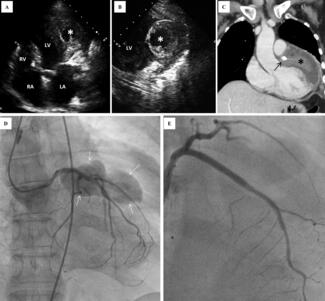

A 64-year-old woman who underwent percutaneous coronary intervention to the proximal left anterior descending artery 2 months prior presented to the emergency room with non-ST segment elevation myocardial infarction. Transthoracic...